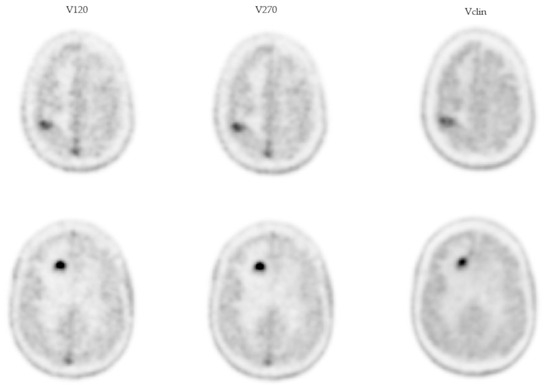

3.2. Dynamic Presentation of Concentrations and Counting Statistics

- 2.19 (1.58; 2.80) and 4.87 (3.16; 11.17) for RN and MP, respectively, with regard to the V120 volume;

- 1.96 (1.32; 2.30) and 4.56 (2.96; 11.46) for RN and MP, respectively, with regard to the V270 volume;

- 1.95 (1.27; 2.28) and 2.70 (2.22; 5.75) for RN and MP, respectively, with regard to the Vclin volume.